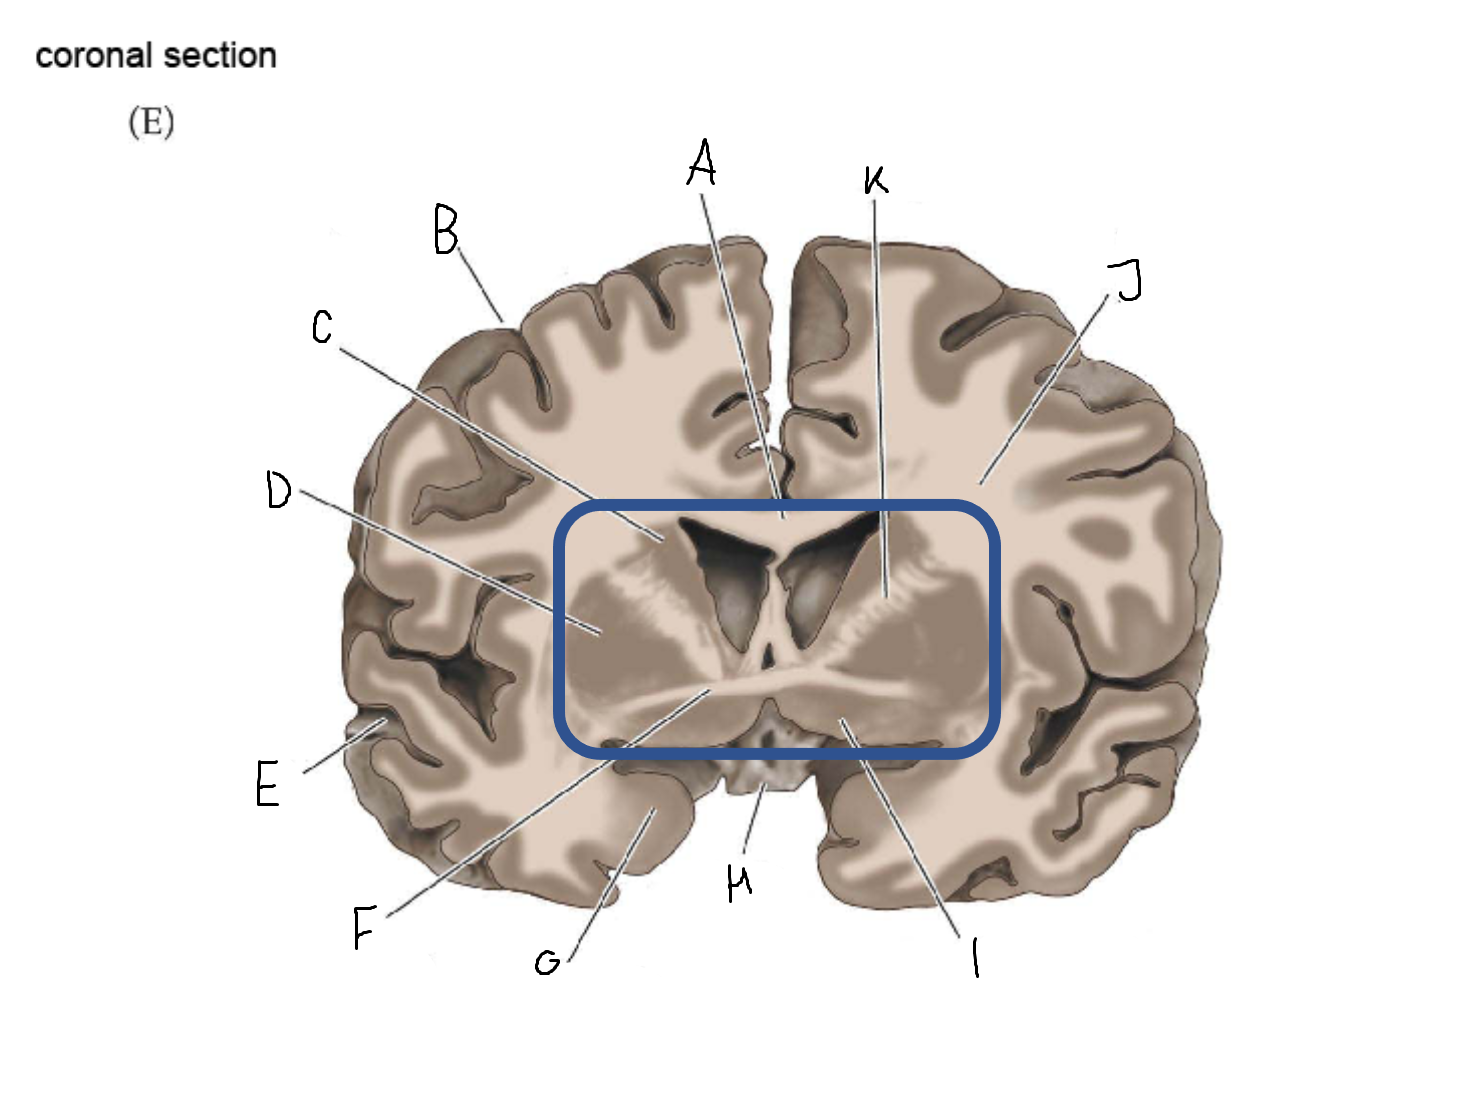

B

anterior horn of lateral ventricle

C

head of caudate nucleus

D

internal capsule (anterior limb)

E

putamen

F

globus pallidus

G

Thalamus

H

External capsule

I

internal capsule (posterior limb)

J

tail of caudate nucleus